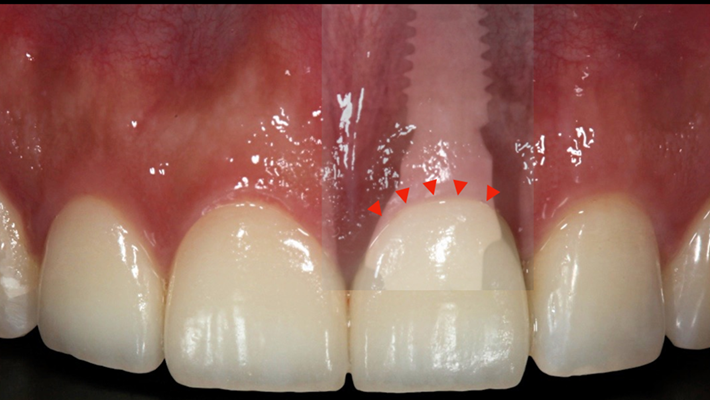

Clinical case: : R2GATE guided surgery & immediate implant placement

- Courtesy of Dr. Kwang Bum Park, Korea -

Dr. Kwang Bum Park, immediate loading, digital guided surgery, digital ONE-DAY implant, maxillary anterior, #21, guided surgery, immediate loading, AnyRidge, R2GATE, Mega ISQ, MEG Torq, R2GATE Full Surgical Kit

implant system, R2GATE Guide, R2GATE full surgical kit, Mega ISQ